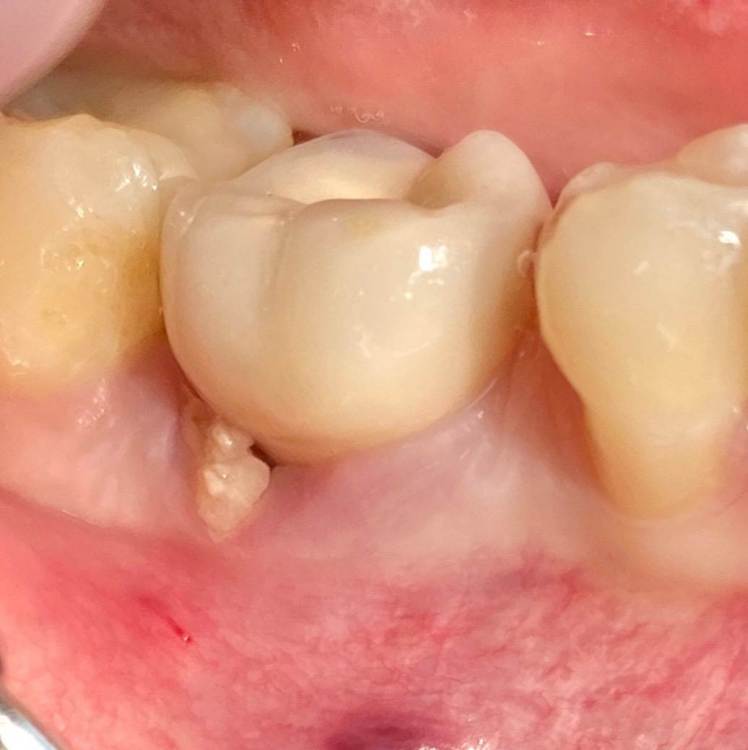

колесников Опубликовано 5 июля, 2022 Поделиться Опубликовано 5 июля, 2022 Здравствуйте коллеги. Год назад попалась публикация где описывался случай как ксеноаугментат секвестрировался спустя 12лет. Мне на днях попался аналогичный случай. Спустя 5 лет(графт bio-oss). Пусковым механизмом, вероятно ,был цемент ,попавший в придесневую шахту после фиксации. Ещё из интересного: интегрированный имплант (mis)удалён ключом на реверс. Вывод: чистый ксено-это не кость. 6 Ссылка на комментарий

колесников Опубликовано 6 июля, 2022 Автор Поделиться Опубликовано 6 июля, 2022 Дискомфорты только недавно появились. Консервация лунки не зло,нужно просто не сыпать чистый ксено. Используйте кортикальный алло и все будет отлично. 2 Ссылка на комментарий